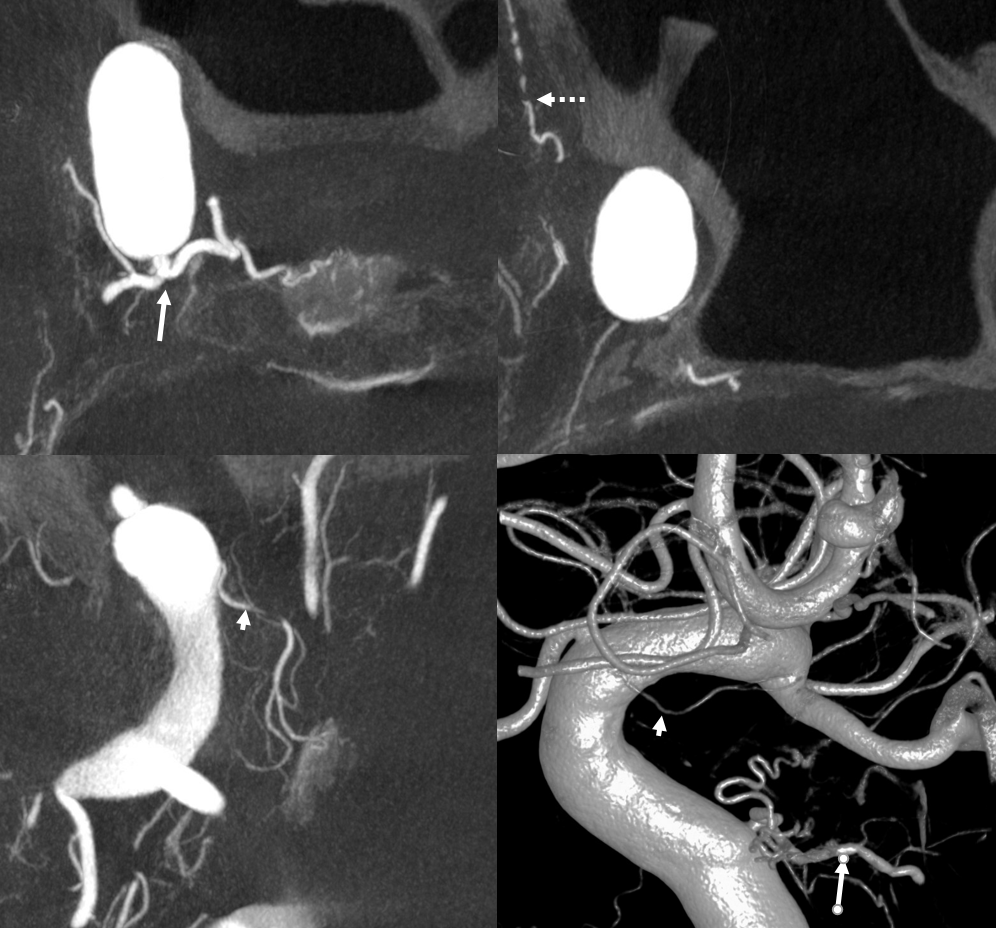

Even the smallest superior hypophyseal arteries can be seen with advanced cone beam CT. Top left is an already high resolution cone beam CT volume rendered image with no apparent Superior Hypophyseal. Windowing to increase sensitivity allows for visualization of a tiny superior hypophyseal (arrow) — top right image. Bottom row are axial (left) and coronal (right) MIP images, showing the same artery, as well as beautifully seen pituitary stalk (dashed arrow)

Superior hypophyseal supply of the Optic Nerve

Important point here — since with increasing visualization of this vessel comes possibility of intervention there. Here is an example of superior hypophyseal artery (arrows) supplying the intracranial and optic canal portions of the nerve (dashed arrows). Any ischemia here (posterior ischemic optic neuropathy) would be quite obvious to the patient. Careful now…

Balance — MHT (with inferior hypophyseals) is large (arrow), also supplying anterolateral territory (dashed arrow) of correspondingly hypoplastic ILT. A superior hypophyseal artery is shown by arrowhead

Anterior-posterior balance

Usually the anterior branch is largest. Here, the posterior branch (arrows) is larger, and supplies the hypophysis in a “recurrent” fashion. See PCOM balance below also

PCOM– superior hypophyseal balance

The balance between these two is rarely discussed. You saw the anastomoses between the two above? Thats one proof of a relationship. The other is that they share supply to the optic apparatus AND anterior pituitary. Here, superior hypophyseal is markedly hypoplastic (dashed arrow). Supply to pituitary and optic chiasm is via a prominent branch (arrows) from the proximal PCOM

PCOM or Superior Hypophyseal? See below. We have all seen those “proximal PCOMs” Well, maybe not — could that really be a superior hypophyseal? Spectrum? Below is something that would normally be called a PCOM aneurysm

DYNA — dashed arrows point to a more proximal superior hypophyseal supplying the upper stalk. Then comes aneurysm and its bigger branch (open arrows) — a pseudo-PCOM if you will. It also contributes to supply of the lower pituitary stalk (solid arrows). The rest goes to the thalamus — as would a PCOM. There is no obvious connection to the PCA. Which is another curious question — when is a PCOM not a PCOM based on that. If you think these are irrelevant pontifications — they are not. Think of what is the territory at risk if this aneurysm is to be treated. And what is the best method? Coiling? Flow Diversion? Clip? Not so irrelevant anymore…

No labels

Another PCOM supply of pituitary — hypoplastic anterior superior hypophyseal branch (dashed arrow), PCOM (arrowhead) supply of pituitary and optic apparatus (arrows)

Largest PCOM supply — note very small classic location superior hypophyseal (dashed arrow). Large PCOM origin supply to pituitary (arrows). Note aneurysm (superior hypophyseal maybe?) and relatively distal origin of the ophthalmic

Posterior Pituitary Supply — MHT Balance

Excellent example of contralateral balance. On the left, there is a hypoplastic posterior hypophyseal network (part of MHT, arrowhead), and a prominent superior hypophyseal artery (associated with a small aneurysm). On the right, the opposite is true — large inferior hypophyseal arteries (dashed arrows) extending past midline due to contralateral hypoplasia, and a smaller superior hypophyseal, without aneurysm — not visible on these VRs, but seen on subsequent MIP images

MIP images — there is a small right superior hypophyseal artery present

Another example

Spectrum and balance again. Usually, the inferior hypophyseal branches from the MHT supply the posterior pituitary. Here, the MHT is well-developed, but primarily supplies the free margin of the tentorium, while the posterior pituitary is fed by the superior hypophyseal branch (arrow).

Same case MHT — the larger trunk (dashed arrow) is mainly marginal tentorial, smaller one (arrowheads) is clival branches inferiorly towards anastomoses with ascending pharyngeal counterparts

Same case MHT — the larger trunk (dashed arrow) is mainly marginal tentorial, smaller one (arrowheads) is clival branches inferiorly towards anastomoses with ascending pharyngeal counterparts

Yet another one — large anterior branch (with infundibulum), no ipsilateral MHT supply

See smaller “middle” hypophyseal as well